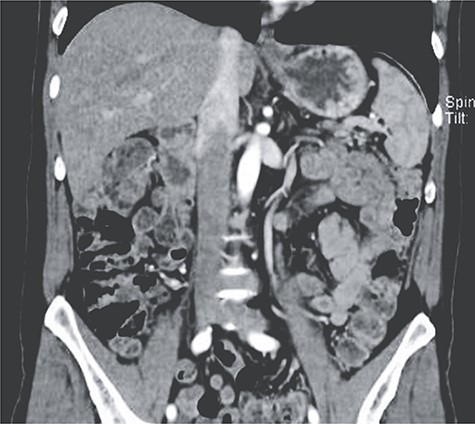

(A) Contrast-enhanced CT showing splenic infarction with inflammatory changes; (B) CT showing free liquid with a hypodense lesion.

Two weeks after discharge, he developed a high fever and acute abdominal pain in his upper left abdomen. Diffuse abdominal tenderness was detected and complementary exams revealed leukocytosis, neutrophilia, elevated C-reactive protein and increased levels of serum procalcitonin. Attributable to his background, a contrast-enhanced abdominal CT was requested detecting an enlarged spleen with a hypodense low-density lesion filled with gas. Free liquid was detected in the abdomen as well (Fig. 2A and B).